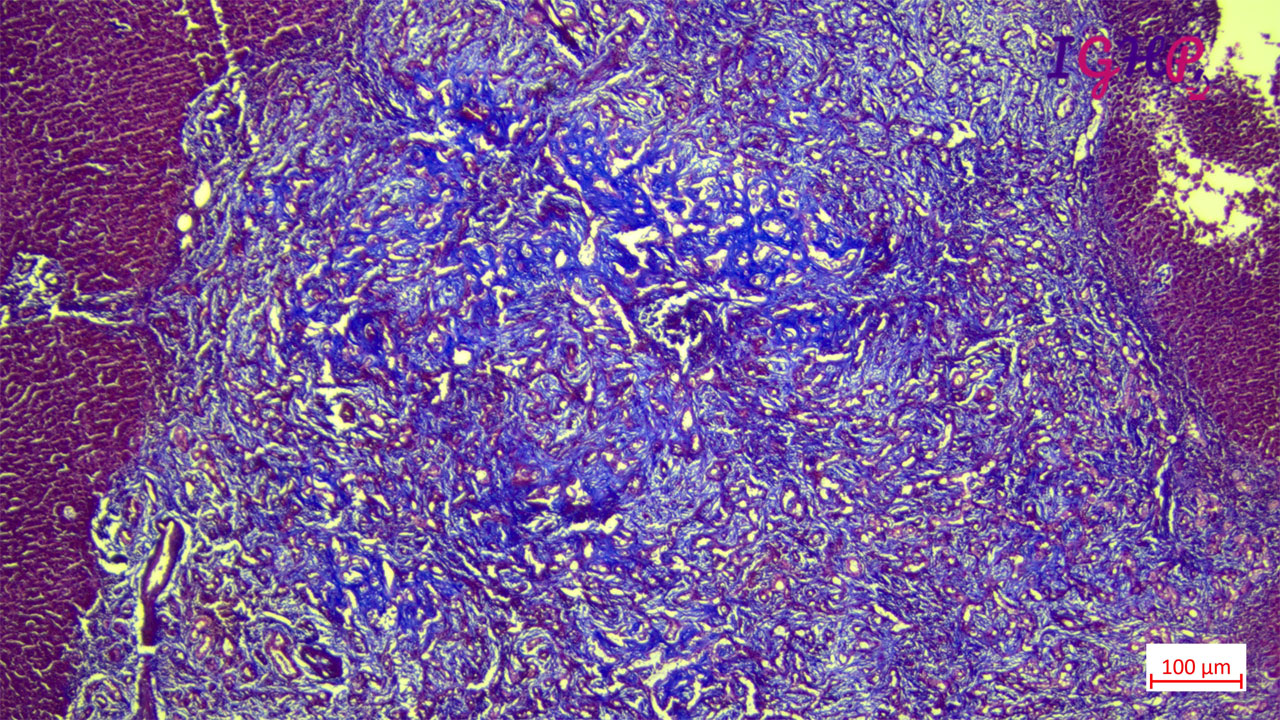

MT Stain highlighted areas of fibrosis